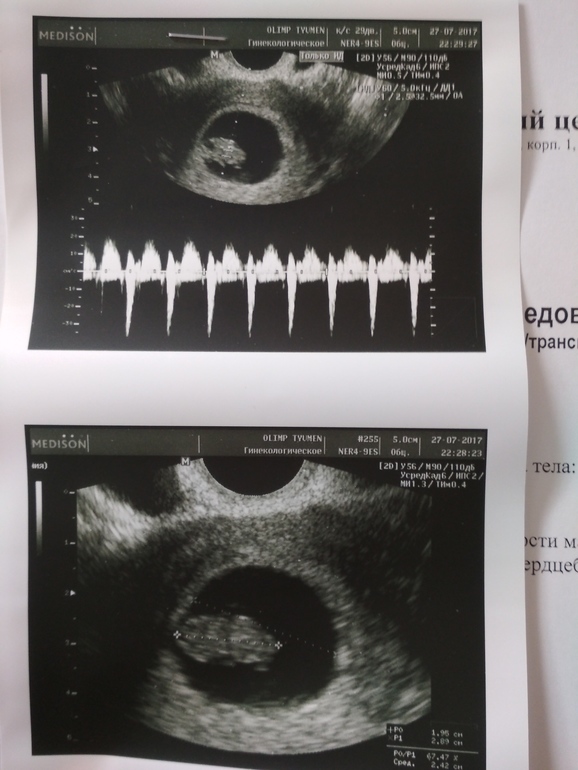

Узи и сердцебиение ❤️

УЗИ, КТГ, доплерВсем, привет! Ну вот и прошли 3 недели, очень они уж долгими и волнительными показались показались. Ну в итоге все хорошо.

нам 8.3